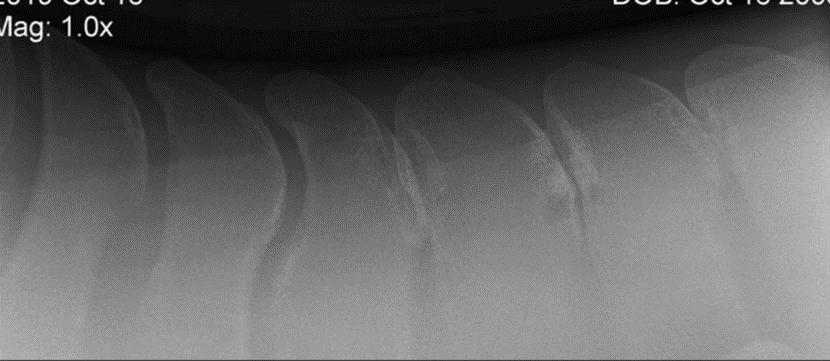

This condition is diagnosed by a veterinarian upon radiographic detection of overriding dorsal spinous processes (ORDSP). Kissing spine diagnosis has increased significantly in recent years due to the increased use of portable X-ray systems, making radiographs easy to do on the farm. [2]

Your veterinarian will perform X-rays along the spine to determine whether the vertebrae in the spine are too close or touching. When examining an X-ray of the back, veterinarians are looking for narrowing of the space between dorsal spinous processes, as well as evidence of bony changes.

In cases of kissing spine, bony remodeling can be seen in the areas where the bones touch. Bone-on-bone contact is painful, so the body attempts to remodel the affected areas in an effort to protect itself.